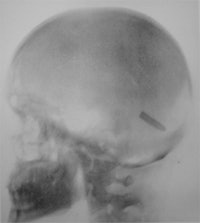

The new high-velocity bullets produced only a small entry wound and often passed straight through the body. The older gaping entrance wounds were no longer seen and army surgeons found that exploration for bullets was often more harmful than careful observation. The introduction of radiography helped in the development of modern war surgery by locating retained bullets. Although the early x-ray tubes were very fragile, the apparatus available before 1900 could detect fractures and foreign bodies.

The first use of x-rays in warfare was in 1896 when Abyssinia was invaded by Italian forces. The Italians lost the battle at Adowa on 1 March 1896, and the casualties returned to the base hospitals in Italy by sea. Lt. Col. Giuseppe Alvaro of the military hospital in Naples successfully took radiographs of two soldiers with forearm fractures. These radiographs were made only six months after the discovery of x-rays and clearly showed the presence of retained bullets. Alvaro stated that the new technique "has proved to be a great aid in diagnosis, enabling us to determine with mathematical precision exactly where a foreign body was located."

In Phalerum a room at the base hospital was set out for the x-ray equipment; Fox Symons had this installed and working by 1 June 1897. Casualties arrived soon after, and x-ray work continued for about six weeks. There were many difficulties, but overall the results were successful. Abbott and Fox Symons were able to illustrate their report about their activities with several radiographs and claimed to "record the first skiagrams taken in wartime, as well as to show that even inexperienced hands working can get fair results." The original prints were exhibited at the first conversazione of the Röntgen Society in London (this became the British Institute of Radiology), which took place in London on 15 November 1897. Abbott and his team treated about 114 patients with war injuries, and Fox Symons probably radiographed about half of them.

There was a long journey to the base hospital at Rawalpindi with transport being slow so the surgeons therefore treated wounds earlier and nearer to the front line. Walter Beevor, a regimental surgeon with the Coldstream Guards, examined 200 cases with x-ray on the Tirah plateau and later took further x-rays in the hospital at Rawalpindi. The examinations included the leg of Gen. Woodhouse whose leg wound had failed to heal, and some weeks later Beevor was able to show the retained bullet. Beevor made a presentation to the United Services Institution in May 1898, which signaled the introduction of field x-ray units into the British Army. It is interesting that Walter Beevor had purchased his apparatus at his own expense.

One hundred and twenty-one wounded were transferred to Abadeih, and in 21 cases the conventional approach could not find a bullet. In 20 of these cases, an accurate diagnosis was made using x-ray, and in the final case the patient was too ill to be examined. Battersby concluded radiography prevented suffering by unnecessary probing of the wound, and in addition to simple radiography he used the cross-thread localization device of James Mackenzie Davidson.